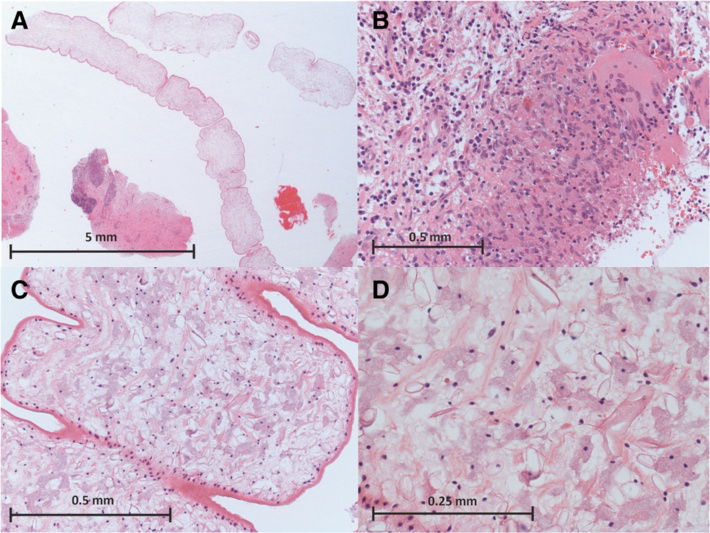

症例は50歳男性。主訴は頭痛およびてんかん発作など。英国在住の中華系で、しばしば故国と行き来をしていた。さしあたってMRIを見るのが手っ取り早い。5枚の前額断MRIの期間は四年間である。白矢印で指されているのが虫体である。症状として、嗅覚異常や記憶のフラッシュバックも起きたらしい。それなんてひぐらし?

病理学的には壊死を伴う肉芽腫性炎症を呈するらしい。

なお、生検で採取された虫体には、口器(mouth parts)や小鉤(hooklets)は含まれていなかったとのこと。つまり、放置していると、またゴソゴソ這い回る可能性がある。患者はalbendazoleを投与され全身状態は良好らしいが、エスカゾール錠の添付文書を見てみると、「海外において、脳を寄生部位とする有鉤嚢虫症患者に本剤を使用した場合、脳内の死滅虫体による炎症性反応の結果として、けいれん発作、頭蓋内圧上昇及び局所神経徴候等の神経症状が発現し、死亡に至ったとの報告がある」との記載もあり、おちおち安心してもいられない。